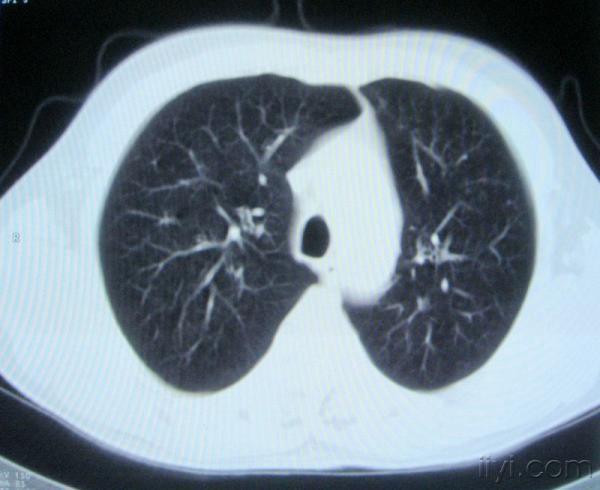

男。60岁,胸片示支气管炎治疗后复查CT。

你指那个肯定是淋巴结,中央系坏死,这很常见,特别在双侧腹股沟会经常看到。这个双侧腋窝及纵隔见多发小淋巴结征。

根据位置考虑应该是淋巴结,密度不均,是因为肿大的淋巴结中心液化坏死